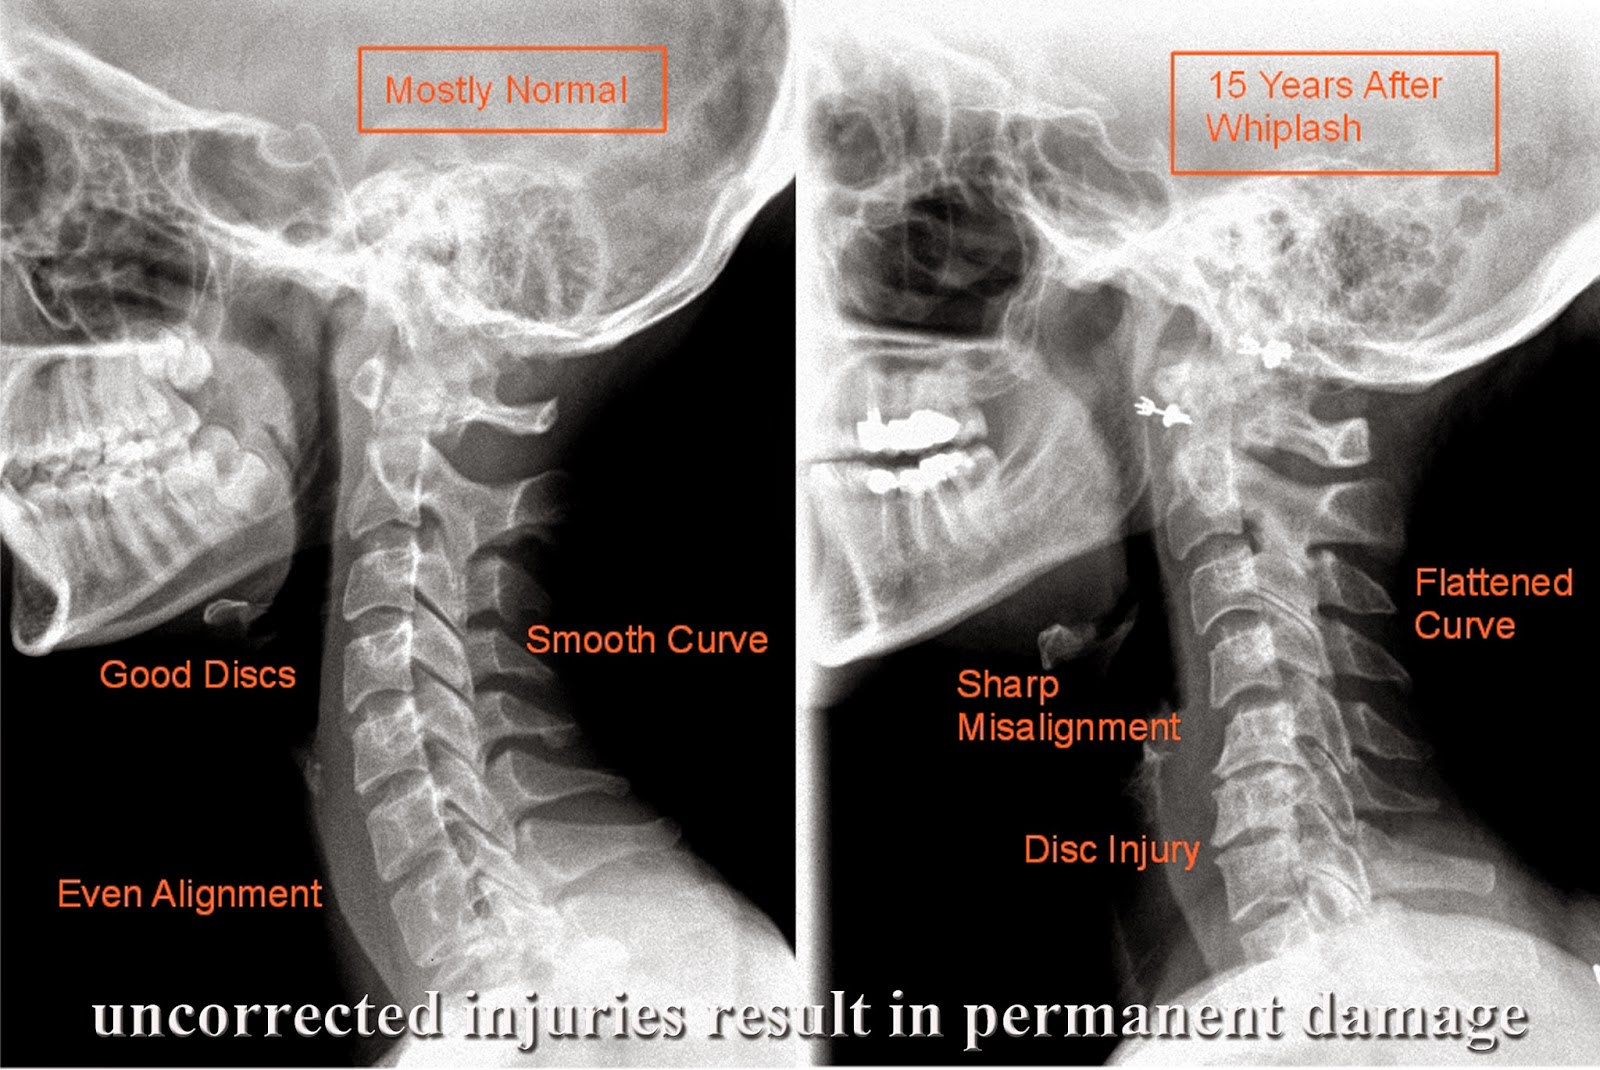

This is what happens when you do not get the proper care after a whiplash injury!

Often patients think that they have not been injured after a car accident. They  might feel some stiffness maybe an ache or two. Then 2 weeks later you wake up and can barely move your neck, or you find you are have constant headaches, or worst. If you do not get the misalignment corrected, the vertebrae as well as the disc will decay and wear prematurely.

Research shows that left untreated, you most likely will end up with some type of permanent damage. Don't wait till it is too late, Get checked today!